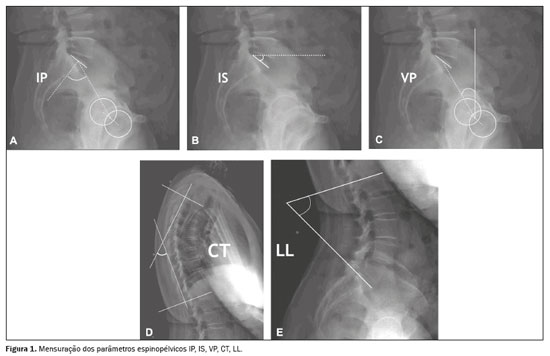

Para mensurar os parâmetros espinopélvicos e ângulos das curvaturas vertebrais foi utilizado o software Surgimap (Nemaris Inc., New York, NY, EUA). Os seguintes parâmetros foram avaliados: inclinação sacral (IS); versão pélvica (VP); incidência pélvica (IP); lordose lombar (LL); cifose torácica (CT); eixo vertical sagital (EVS); ângulo espinossacral (ASS); ângulo T1 pélvico (ATP) e versão global (VG), conforme mostrado nas Figuras 1 e 2. A IS corresponde ao ângulo formado entre a placa da extremidade superior de S1 e a linha horizontal. A VP corresponde ao ângulo formado entre uma linha vertical que se origina no centro da cabeça femoral e uma linha que parte do centro da cabeça femoral para o ponto médio da placa terminal de S1. A IP corresponde ao ângulo formado pela perpendicular ao platô sacral e a linha que conecta o ponto médio deste com o centro de rotação femoral. A LL é a medida do ângulo de Cobb do platô superior de S1 até o platô superior de L1. A CT é a medida do ângulo de Cobb do platô inferior de T12 até o platô superior de T1. O EVS é a medida da distância horizontal entre a linha de prumo de C7 e a linha vertical que passa pelo ponto posterossuperior de S1. O ASS corresponde ao ângulo formado entre a linha que passa do centro de C7 ao centro da placa terminal de S1 e a superfície da placa terminal sacral. O ATP é o ângulo obtido por uma linha formada do centro geométrico das cabeças femorais ao centro do corpo vertebral T1 e uma linha do centro geométrico das cabeças femorais ao centro da placa terminal superior de S1. A VG é definida como o ângulo formado por uma linha do centro da placa final superior sacral ao centro do corpo vertebral C7 e uma linha do centro geométrico das cabeças femorais ao centro da placa terminal sacral(15). Os contornos das cabeças femorais foram marcados e foram traçadas linhas adjacentes ao platô superior de S1, platô superior de L1, platô inferior de T12, platô superior de T1 e platô inferior de C2. A partir dessas marcações, o software calculou automaticamente os parâmetros espinopélvicos e as curvaturas vertebrais.